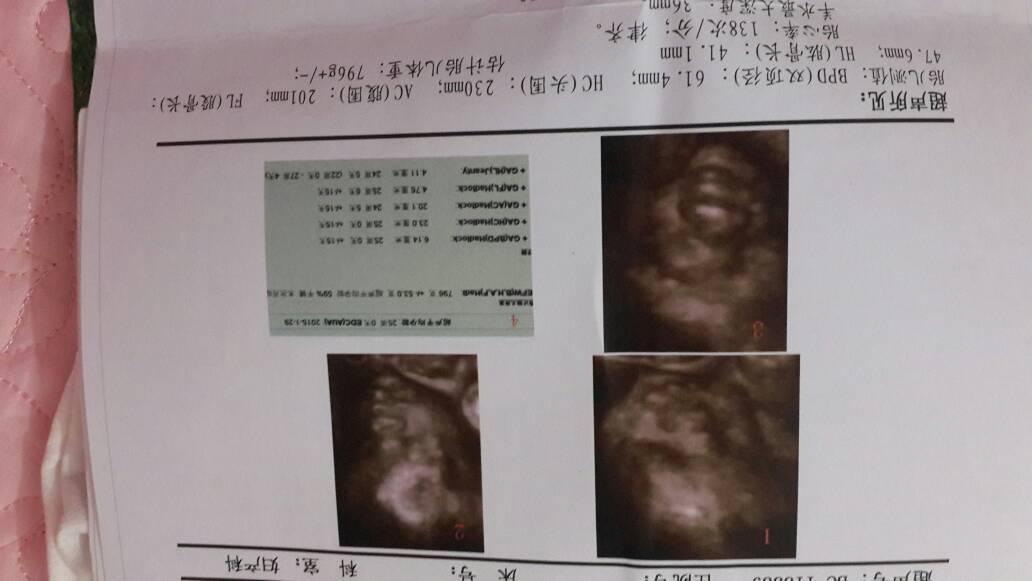

做完四维啦,宝宝健康,亲们谁能帮我看看是男宝女宝啊 做完四维啦,宝宝健康,亲们谁能帮我看看是男宝女宝啊😄 点击展开 微风永相伴 2014-10-18 14:46 为您推荐: 其他回答 亲男女都一样 诗语_pWkb 2014-10-18 15:56 这是看不出来的,虽然彩超是可以鉴定性别的,但是一般的不告诉你的,因为是违法的 我是学霸306 2014-10-18 15:26 宝宝很健康哦,这个看不出男女的 院芊芊 2014-10-18 15:10 这个可能要那位做四維才看电脑才知吧 ※Lin¤淳※ 2014-10-18 15:03 健健康康就好 一诺妈妈 2014-10-18 14:51 加载更多 相关问题 做完四维啦,宝宝健康,亲们谁能帮我看看是男宝女宝啊😄 想让亲们的火眼金睛帮我看看,是男宝女宝,家里人大多觉得是女宝,我也是,不喜勿喷,谢谢 刚做的三维,接健康宝宝,祝各位妈妈好运,大家帮我看看是男宝还是女宝?